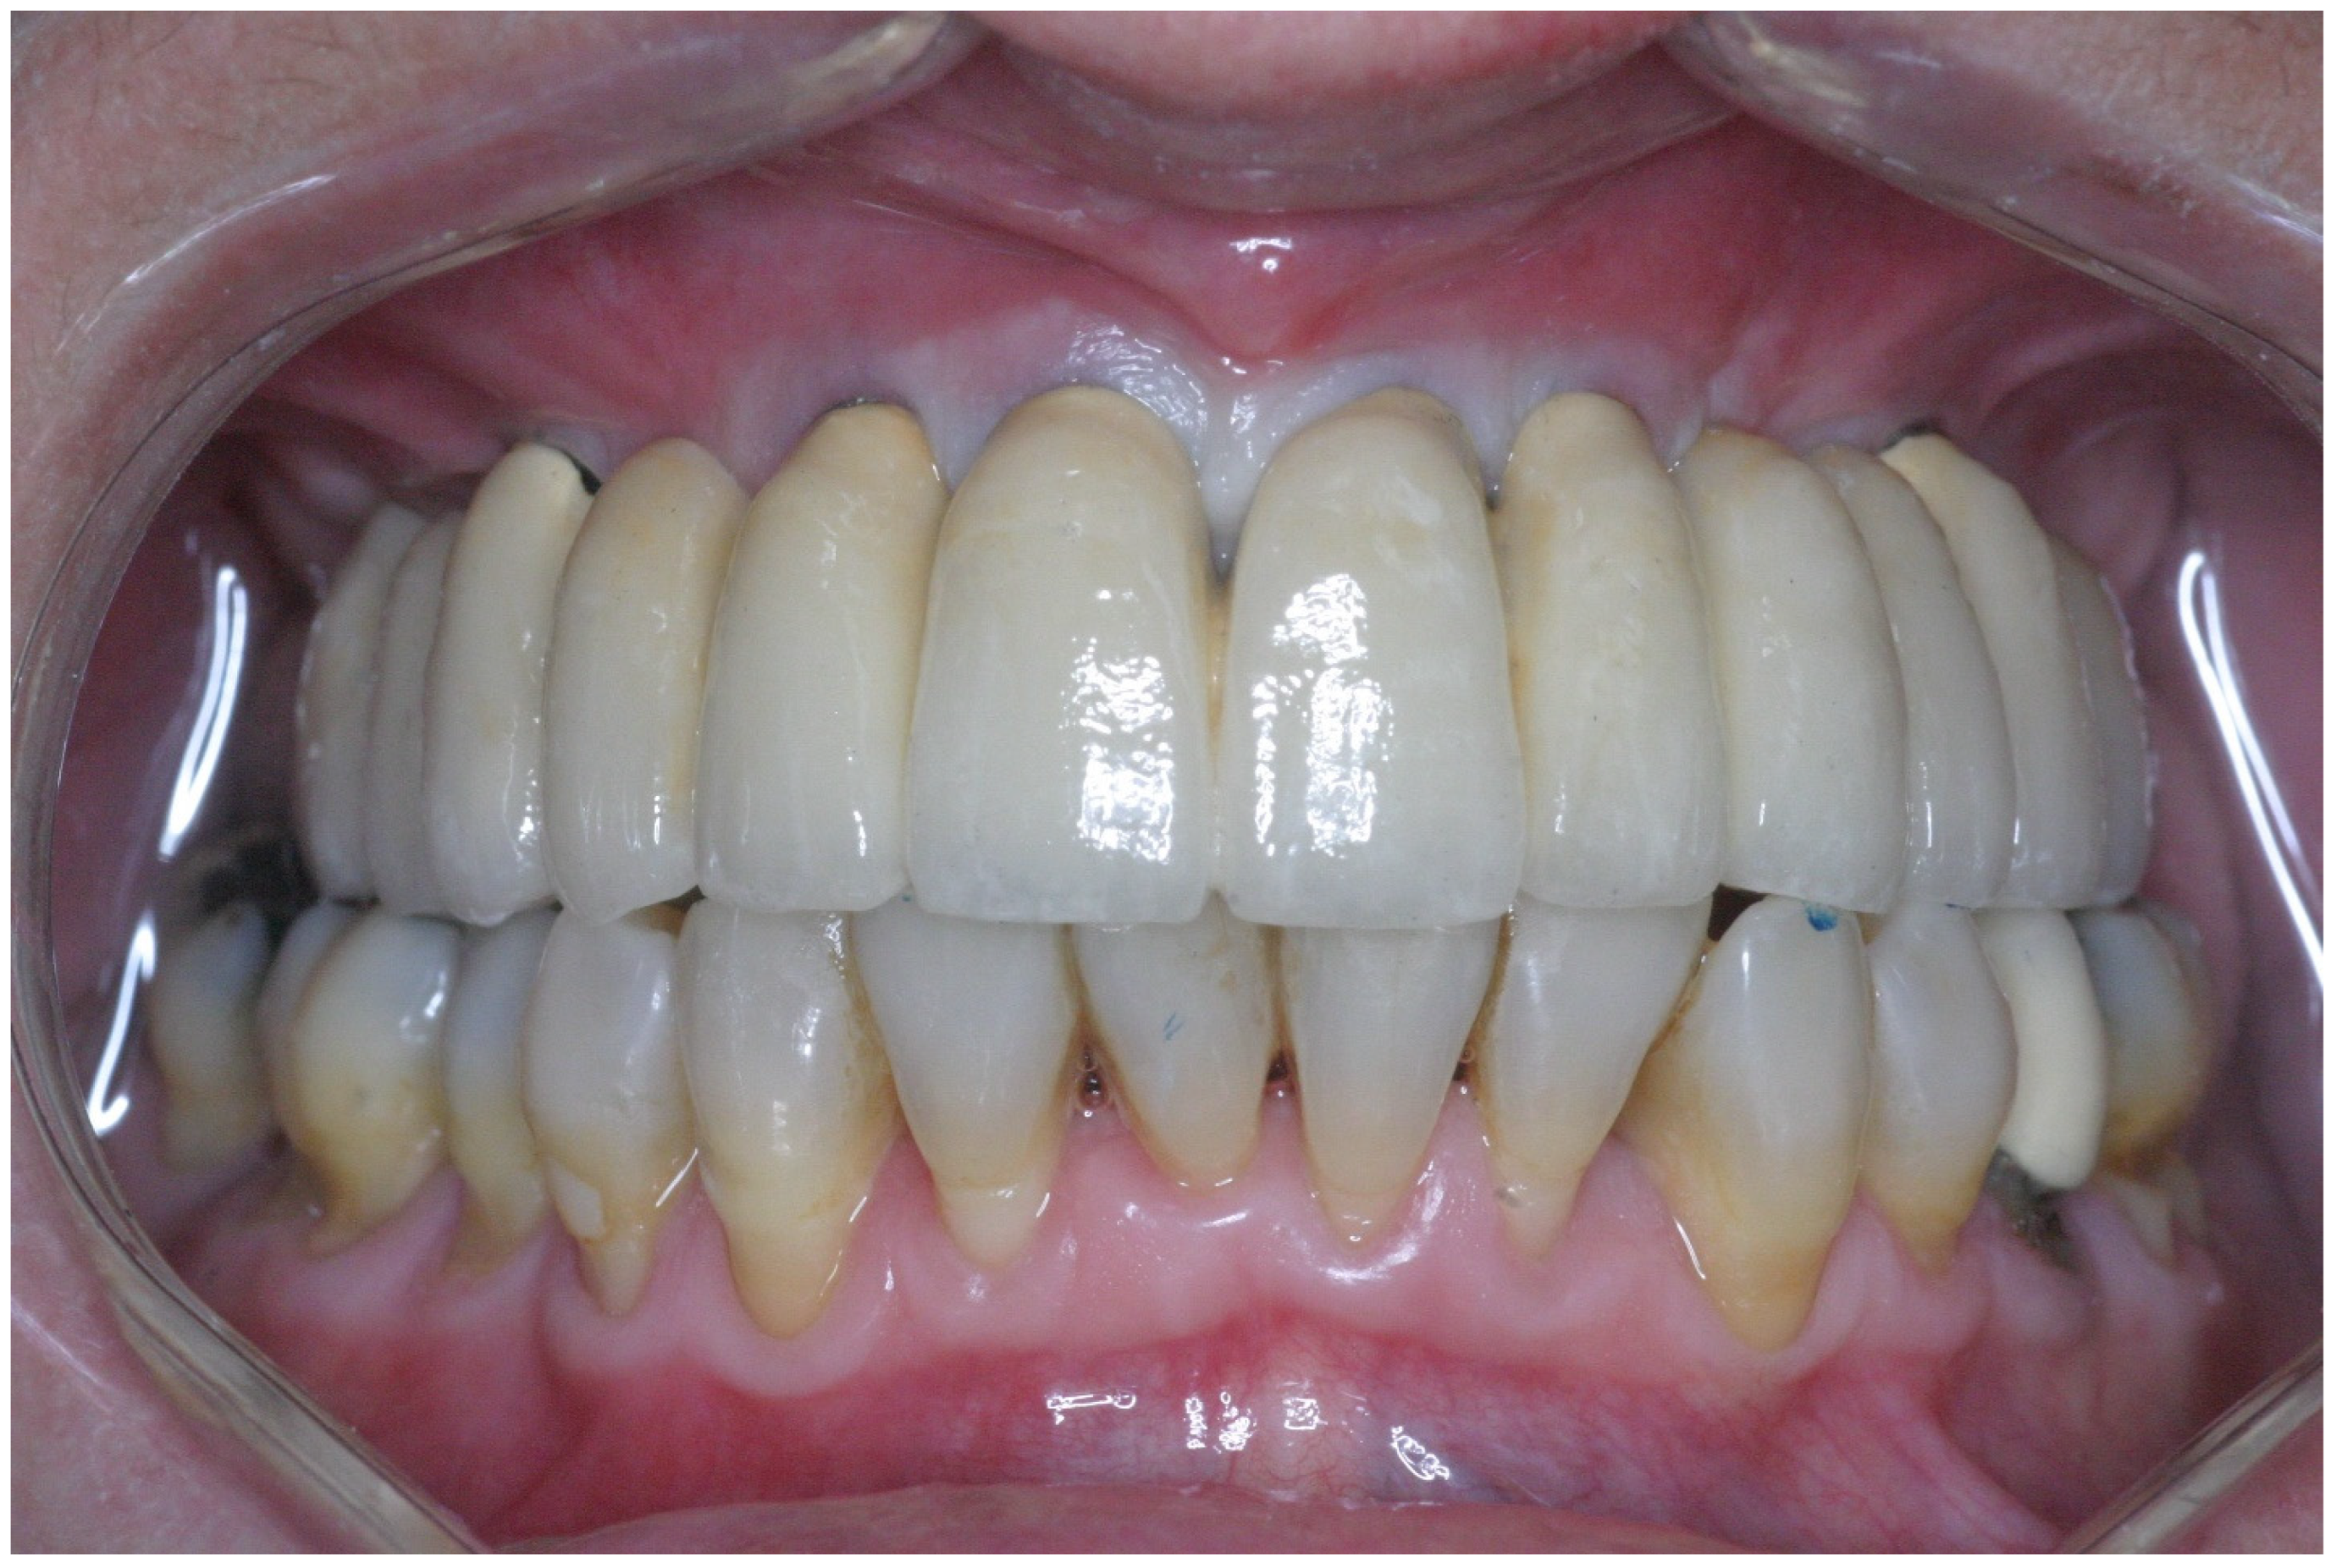

2.3. Prosthetic Protocol

Clinical Follow-Up Examination